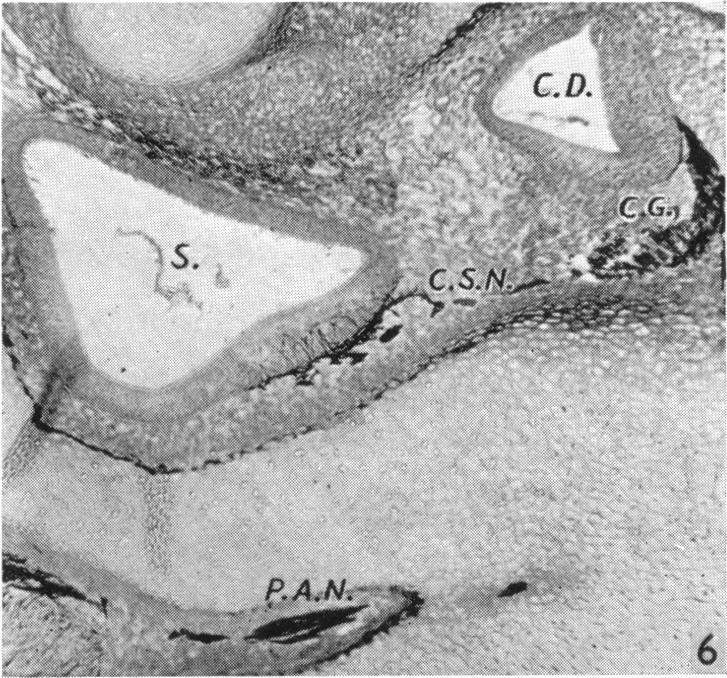

Nervous pathways in the developing human labyrinth.

J Anat. 1951 Oct;85(4):359-69.